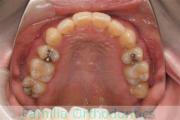

No.22V-409

- 主な症状:

- 叢生

- 年齢:

- 16歳

- 性別:

- 女性

- 抜歯部位

- 上:

- 44

- 下:

- 8|58

- 主な使用装置:

- FEA

- 治療にかかった費用:

- 86万円

八重歯を治したいということで来院されました。下あごの左ずれのある上顎前突(出っ歯)・叢生(でこぼこ)でしたので、上は左右から、下はで左のみ小臼歯を抜歯して、歯科矯正用アンカースクリューとマルチブラケット法にて治療を行いました。2年強、30回程度の通院が必要でした。

上下とも前歯の叢生(でこぼこ、凹凸、ガタガタ)があるため、保定を怠ると後戻りのリスクがあります。